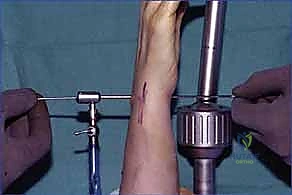

K-wire Fixation: Once an optimal reduction is achieved, we will temporarily stabilize the scaphoid and lunate using K-wires.

- Typically, we'll insert two 0.045-inch or 0.062-inch K-wires.

- One K-wire will pass from the scaphoid into the lunate, traversing the reduced scapholunate interval.

- A second K-wire will pass from the lunate into the triquetrum, or from the scaphoid into the capitate, to further stabilize the carpus and maintain the reduction.

- Ensure the K-wires are placed to avoid future tunnel drilling sites and are not impinging on articular surfaces.

Surgical Warning: K-wire placement must be precise. Avoid violating the midcarpal or radiocarpal joint spaces. Confirm placement with multiple fluoroscopic views (PA, lateral, oblique) to ensure proper carpal alignment and avoid iatrogenic injury. Overtightening the reduction can lead to stiffness; aim for a stable, anatomical reduction.

TECH FIG 3 • A. K-wires are used to reduce the scapholunate interval.